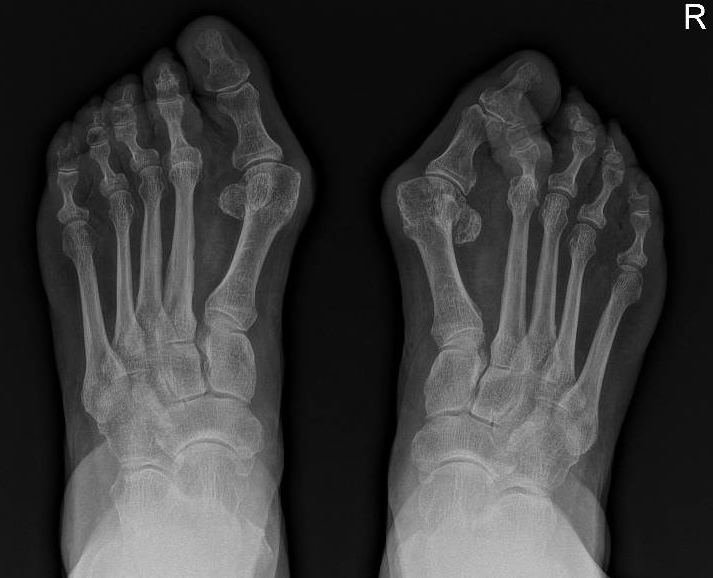

De diagnose wordt gesteld aan de hand van een klinisch onderzoek in combinatie met de nodige staande radiografieën van de beide voeten.